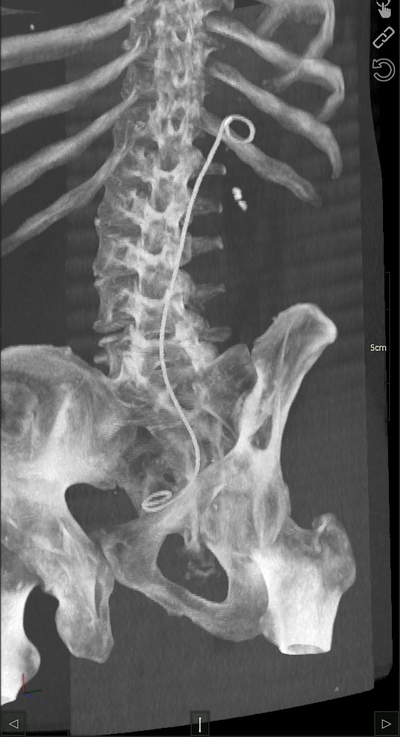

Радуйтесь что так не развлекали. А если кровь не проверяли и было бы осложнение (вроде как) то можно всю жизнь потом на диализ ходить

Иллюстрация к комментарию

раскрыть ветку (1)